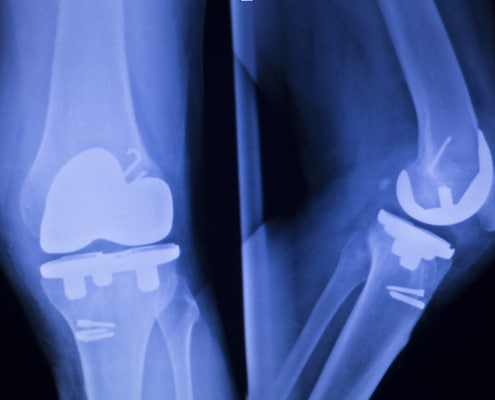

Total Knee Replacement Surgery: What to Expect

Total knee replacement surgery can provide positive outcomes…

What’s the difference between total knee replacement surgery and partial knee replacement surgery?

Comparing total knee replacement surgery vs. partial knee replacement…

Types of Knee Implants

The types of knee Implants used in total knee replacement surgery…